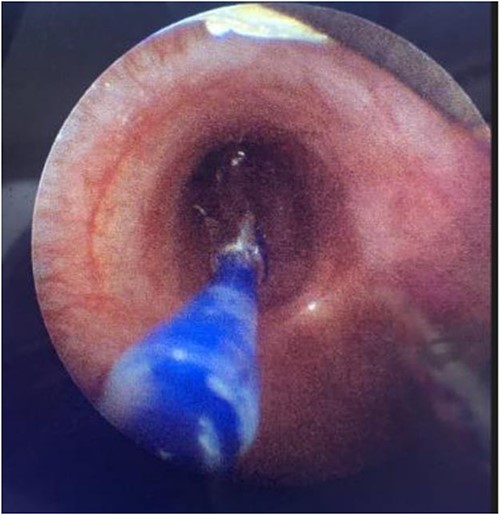

During the procedure in the catheter lab, our team placed a 5 mm balloon over a 3.5 mm bronchoscope, shown in Fig. 1, through the suction port and advanced to the level of the carina. Utilizing fluoroscopy, the balloon was advanced to the narrowed portion of the left main stem bronchus. After this placement was confirmed, the interventional cardiology team tunneled their balloons into the left pulmonary artery and aorta. Markers on the balloons were utilized to ensure the airway and intravascular balloons were adjacent. At this time, both intravascular balloons and the bronchial balloon were simultaneously inflated under direct fluoroscopic visualization, shown in Fig. 2. The bronchial balloon was deflated and removed at this time. The left mainstem bronchus was then visualized, whereas the intravascular dilation and stent placement occurred. During this step of the procedure, the left mainstem bronchus appeared wider compared with its preoperative state and no narrowing of the bronchus was observed upon additional intravascular balloon dilation. The patient improved dramatically within the postoperative period, however needed a further cardiac catheterization to dilate his aortic and pulmonary artery stent. Pediatric otolaryngology was again involved to inflate a balloon to prevent further bronchial compression. Once appropriately prepped, we introduced a 3 mm bronchoscope to the left main bronchus. Under direction of the interventional cardiologist, the balloon introduced into the left mainstem bronchus was visualized under fluoroscopy, advanced to the appropriate position determined by the interventional cardiologist, and then inflated. The balloon size was 6 mm in diameter and 20 mm in length and it was inflated to atmospheric pressure and kept inflated while the interventional cardiologist performed their balloon dilation of left pulmonary artery along with a stent placed in the left pulmonary artery and aorta. The balloon was then deflated and withdrawn and the resultant bronchus was larger in comparison to pre-op. The patient tolerated the operation well.

Direct visualization of a 5 mm balloon over a 3.5 mm bronchoscope dilating the left main bronchus.